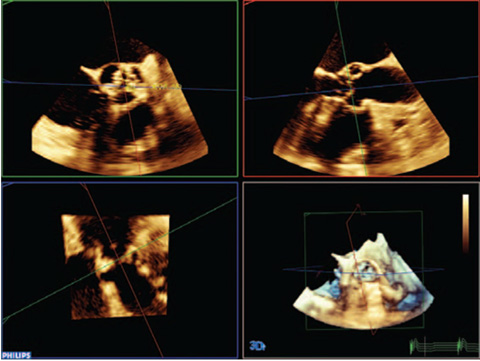

HeartModelᴬ⋅ᴵ⋅— это новое приложение для УЗИ с технологией интеллектуального анализа анатомии (AIUS), предлагающее передовые средства количественной оценки трехмерных данных в реальном времени, автоматизированное создание двумерных проекций и уверенное получение воспроизводимых результатов в эхокардиографии. Приложение HeartModelᴬ⋅ᴵ⋅ автоматически определяет, сегментирует и количественно оценивает левое предсердие (ЛП) и левый желудочек (ЛЖ) в трехмерных объемных данных.

Согласно результатам сравнительного исследования двумерного количественного анализа и анализа в режиме Live 3D HeartModelᴬ⋅ᴵ⋅ приложение HeartModelᴬ⋅ᴵ⋅ позволило сэкономить 82% времени при работе в полностью автоматическом режиме и 71% времени при минимальном ручном редактировании.

Благодаря повышенной воспроизводимости и выполнению меньшего количества этапов за меньший промежуток времени, чем требуется для традиционных методов, больше пользователей смогут увереннее проводить диагностику.